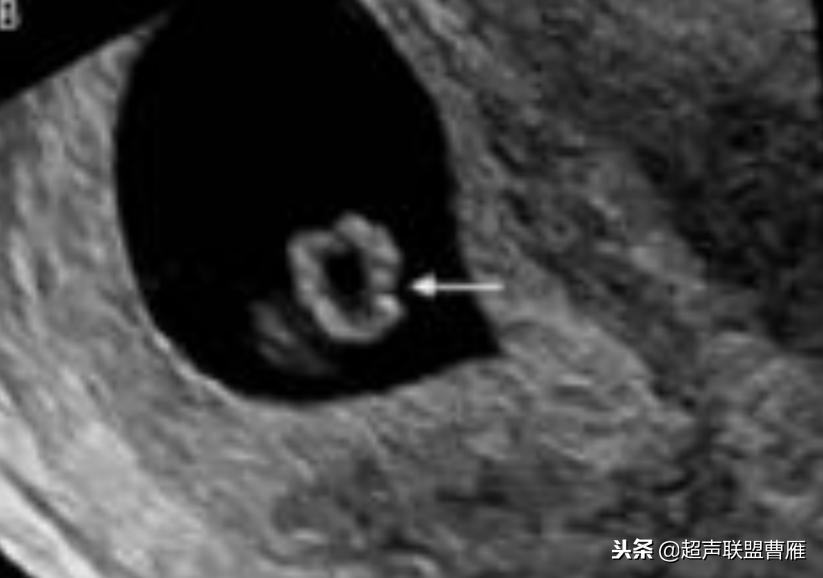

· 正常情况下,卵黄囊中央表现为无回声,周边为厚薄均一、边界清晰的环形高回声。

正常早孕卵黄囊声像图

早孕 胚芽 卵黄囊

5周+ 、6周+ 声像图

孕7周左右(胚芽11mm 卵黄囊)

胎芽 卵黄囊 心管搏动信号

宫内早孕 (7周左右)

正常宫内胚胎策划、卵黄囊